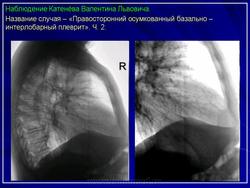

Иллюстрации 1, 2. Теневая картина осумкованного выпота в малой междолевой щели.

Иллюстрации 5, 6. Теневая картина осумкованного выпота в верхних отделах главной междолевой щели.